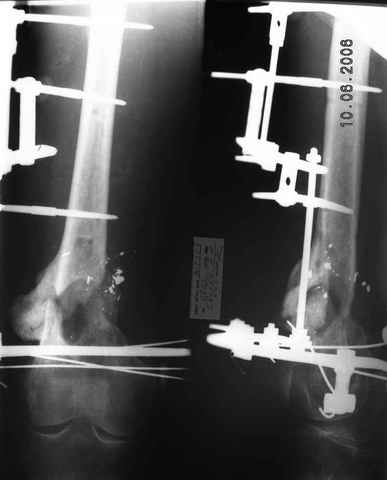

Возможно, проф. Лазарев предложит другой вариант, а в наших условиях мы бы закрыто заштифтовали бы бедро антеградно. Устранили бы варус, используя голень как рычаг, вероятнее всего, даже дистрактор не понадобился бы. В приницпе, можно и ретроградно ири наличии движений в колене, но варус будет труднее устранить - можно и предварительно аппаратом в таком случае.

Стержень можно использовать и обычный потолще, но лучше бы с возможностью введения большего, чем два фронтальных, числа запирающих винтов.

Учитывая наличие этой мощной спайки, запереть можно сразу динамически.